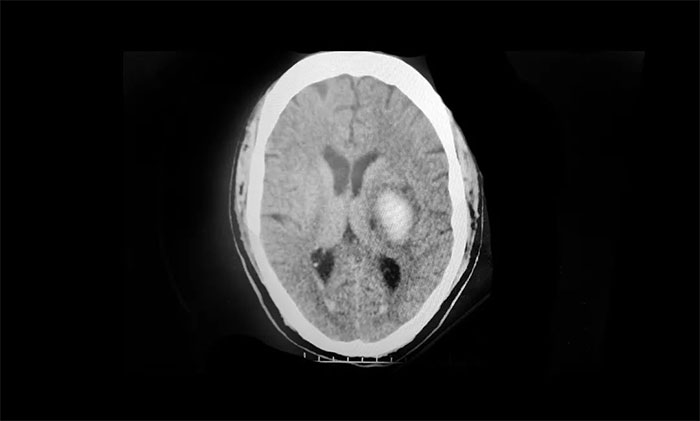

经当地医院头颅CT 检查提示:基底节区脑出血。立即予以脱水降颅内压、营养神经、补液、控制血压、抗感染等对症治疗。后经该院神经外科会诊,考虑有手术指征,建议手术,但家属当时因顾虑手术风险,拒绝了手术治疗的提议。

▲ 左侧基底节区出血

入院后确诊为:1、基底节出血;2、高血压2级;3、Ⅱ型糖尿病;4、肺部感染。同时,病程记录陈先生有5年高血压病史,且未规律服药。“他平时很忙,想起来就吃,想不起来就不吃,断断续续的。”回忆起父亲的服药史,陈女士一脸无奈。